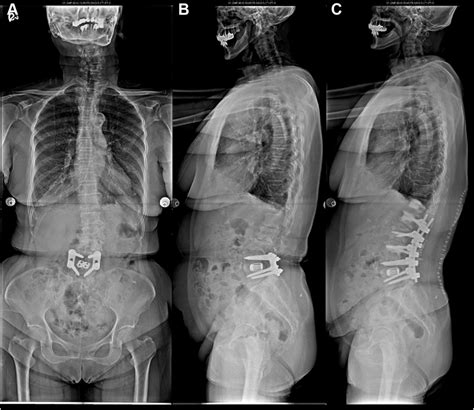

Alright, so how do doctors figure out if you have degenerative retrolisthesis of L1 on L2 ? The diagnostic process typically involves a combination of a physical exam, a review of your medical history, and imaging tests. First, your doctor will likely ask about your symptoms. They’ll want to know when the pain started, what makes it better or worse, and whether you’ve noticed any other symptoms like numbness or weakness. Next, they will perform a physical exam. This involves assessing your posture, range of motion, and reflexes. They may also check for tenderness in your lower back and perform tests to assess nerve function. Imaging tests play a crucial role in diagnosing retrolisthesis. X-rays are usually the first imaging test. They can reveal the slippage of the vertebra and help to rule out other causes of back pain. However, X-rays only show bones, not soft tissues like discs and ligaments. MRI (magnetic resonance imaging) is more detailed and often used to confirm the diagnosis. An MRI uses powerful magnets and radio waves to create detailed images of the spine, including the bones, discs, nerves, and soft tissues. It can show the extent of the slippage and whether any nerves are being compressed. A CT (computed tomography) scan might be used if an MRI is not possible or if the doctor wants a more detailed view of the bones. A CT scan uses X-rays to create cross-sectional images of the spine. The doctor might also order a bone scan to look for signs of arthritis or other bone abnormalities. Nerve conduction studies and electromyography (EMG) might be used if nerve compression is suspected. These tests measure the electrical activity of the nerves and muscles to assess nerve function. The results from all these tests help the doctor confirm the diagnosis of degenerative retrolisthesis of L1 on L2 and determine the best course of treatment. Accurate diagnosis is super important, because the treatment depends on the severity of the condition and the symptoms you are experiencing. So, if you’re experiencing back pain or other symptoms, don’t hesitate to see a doctor. Early diagnosis and treatment can often prevent the condition from getting worse.